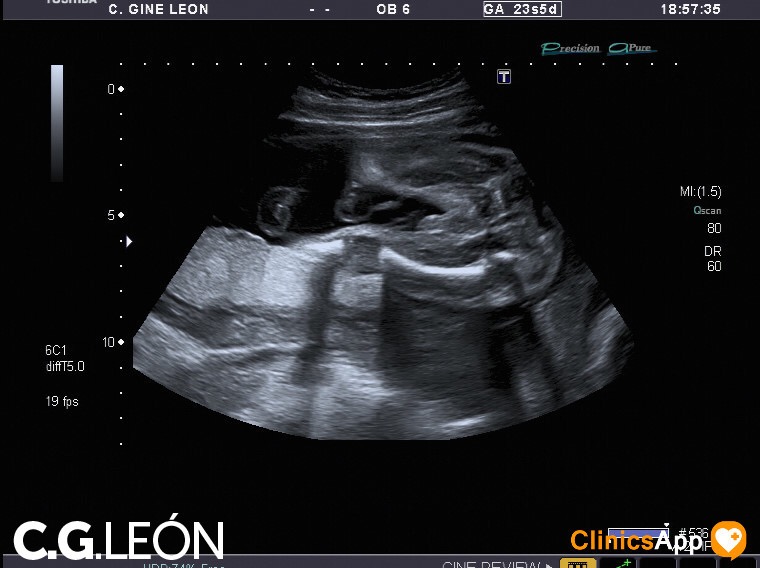

Aquí las fotos de la quinta ecografía, nada que destacar excepto que la ginecóloga estaba de mala leche y no se esmeró demasiado en las fotos. Hay una en la que se ve una mano, en directo se distinguía mejor, claro, porque se vio abierta como en la foto y luego la cerró. Pero por lo general encuentro de difícil interpretación este lote de fotos.